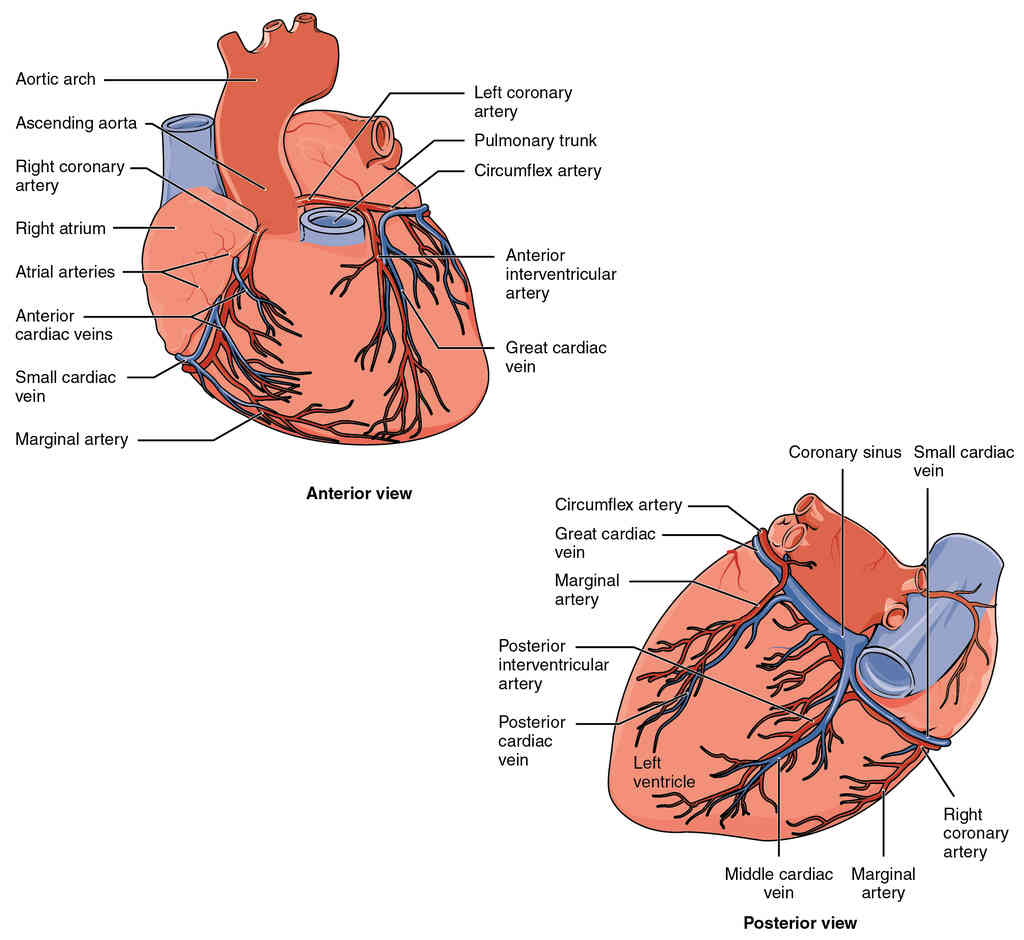

This page is under construction. For now, it is just a resource of the images found in the OpenStax Anatomy and Physiology Handbook. It wil slowly change into a revision tool. Each slide has a number. Use this to refer to the slide. When completed, it will have an unlabelled section, with labelled slides in parallel. On the unlabelled slides, write your answer and use the labelled slide to assess yourself. Keep track by also noting the number on each slide. Improvement at each attempt is important, more so than full marks on a first attempt.